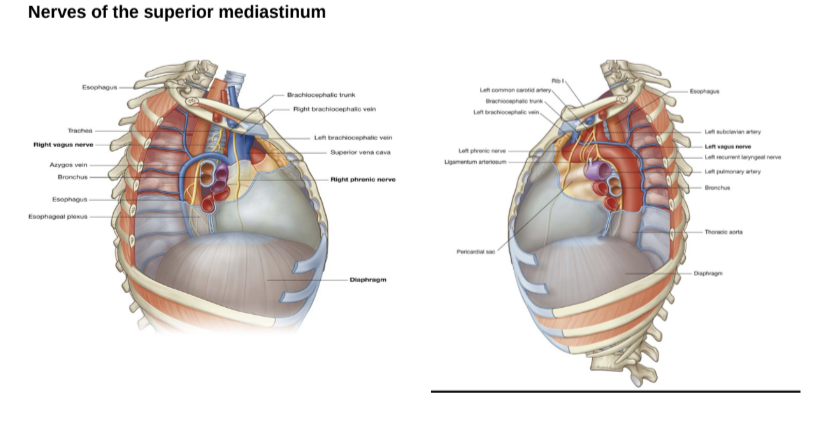

Nerves of the superior mediastinum

At the level of the superior mediastinum we mainly have the vagus & diaphragmatic/phrenic nerve —

Right & left vagus nerves of superior mediastinum

Right vagus nerve —

Enters superior mediastinum between right brachiocephalic vein & brachiocephalic trunk

Then goes down along trachea & passes posterior to roof of right lung then near esophagus to arrive at diaphragm

Left vagus nerve —

Enters mediastinum between left brachiocephalic vein & left common carotid artery

Passes posteriorly to the root of the left lung

At the level in which it crosses to the lateral side of the arch of the aorta there is the origin of the laryngeal nerve

Phrenic nerve? left recurrent laryngeal nerve? slides & sbobina saying different things